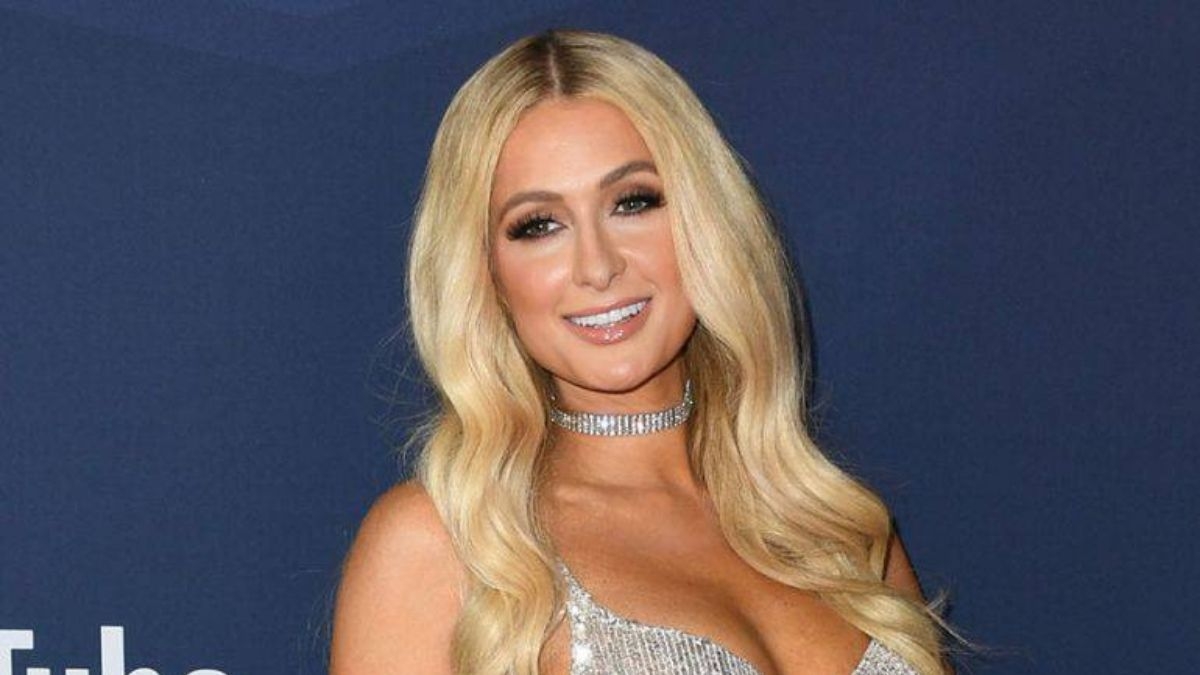

La justicia francesa inició una investigación por "violación del secreto profesional", después que un cirujano intentara subastar una radiografía de una superviviente del ataque yihadista en 2015 contra la sala de conciertos Bataclan, indicó este martes a la fiscalía de París.

Según el medio Mediapart, el reputado cirujano Emmanuel Masmejean sacó a subasta en OpenSea, un sitio especializado en venta de objetos digitales NFT, la radiografía de una superviviente del Bataclan, a la que había operado.

La radiografía muestra uno de sus antebrazos atravesados por una bala de kalashnikov, disparada durante una serie de atentados perpetrados el 13 de noviembre de 2015 en París y sus alrededores que costaron la vida a 130 personas.

El jefe de los hospitales de París (AP-HP) anunció rápidamente que emprenderían acciones legales, denunciando un "acto escandaloso". Según Mediapart, la radiografía tenía un precio de salida de 2.776 dólares.

En un comunicado enviado por su abogada, la superviviente se dijo "muy conmocionada" por este intento de remate y por el "desprecio" del médico.

El médico escribió en su cuenta Twitter que lamentaba este "error", precisando a su vez que destruyó "la obra en cuestión" y que no obtuvo beneficios.